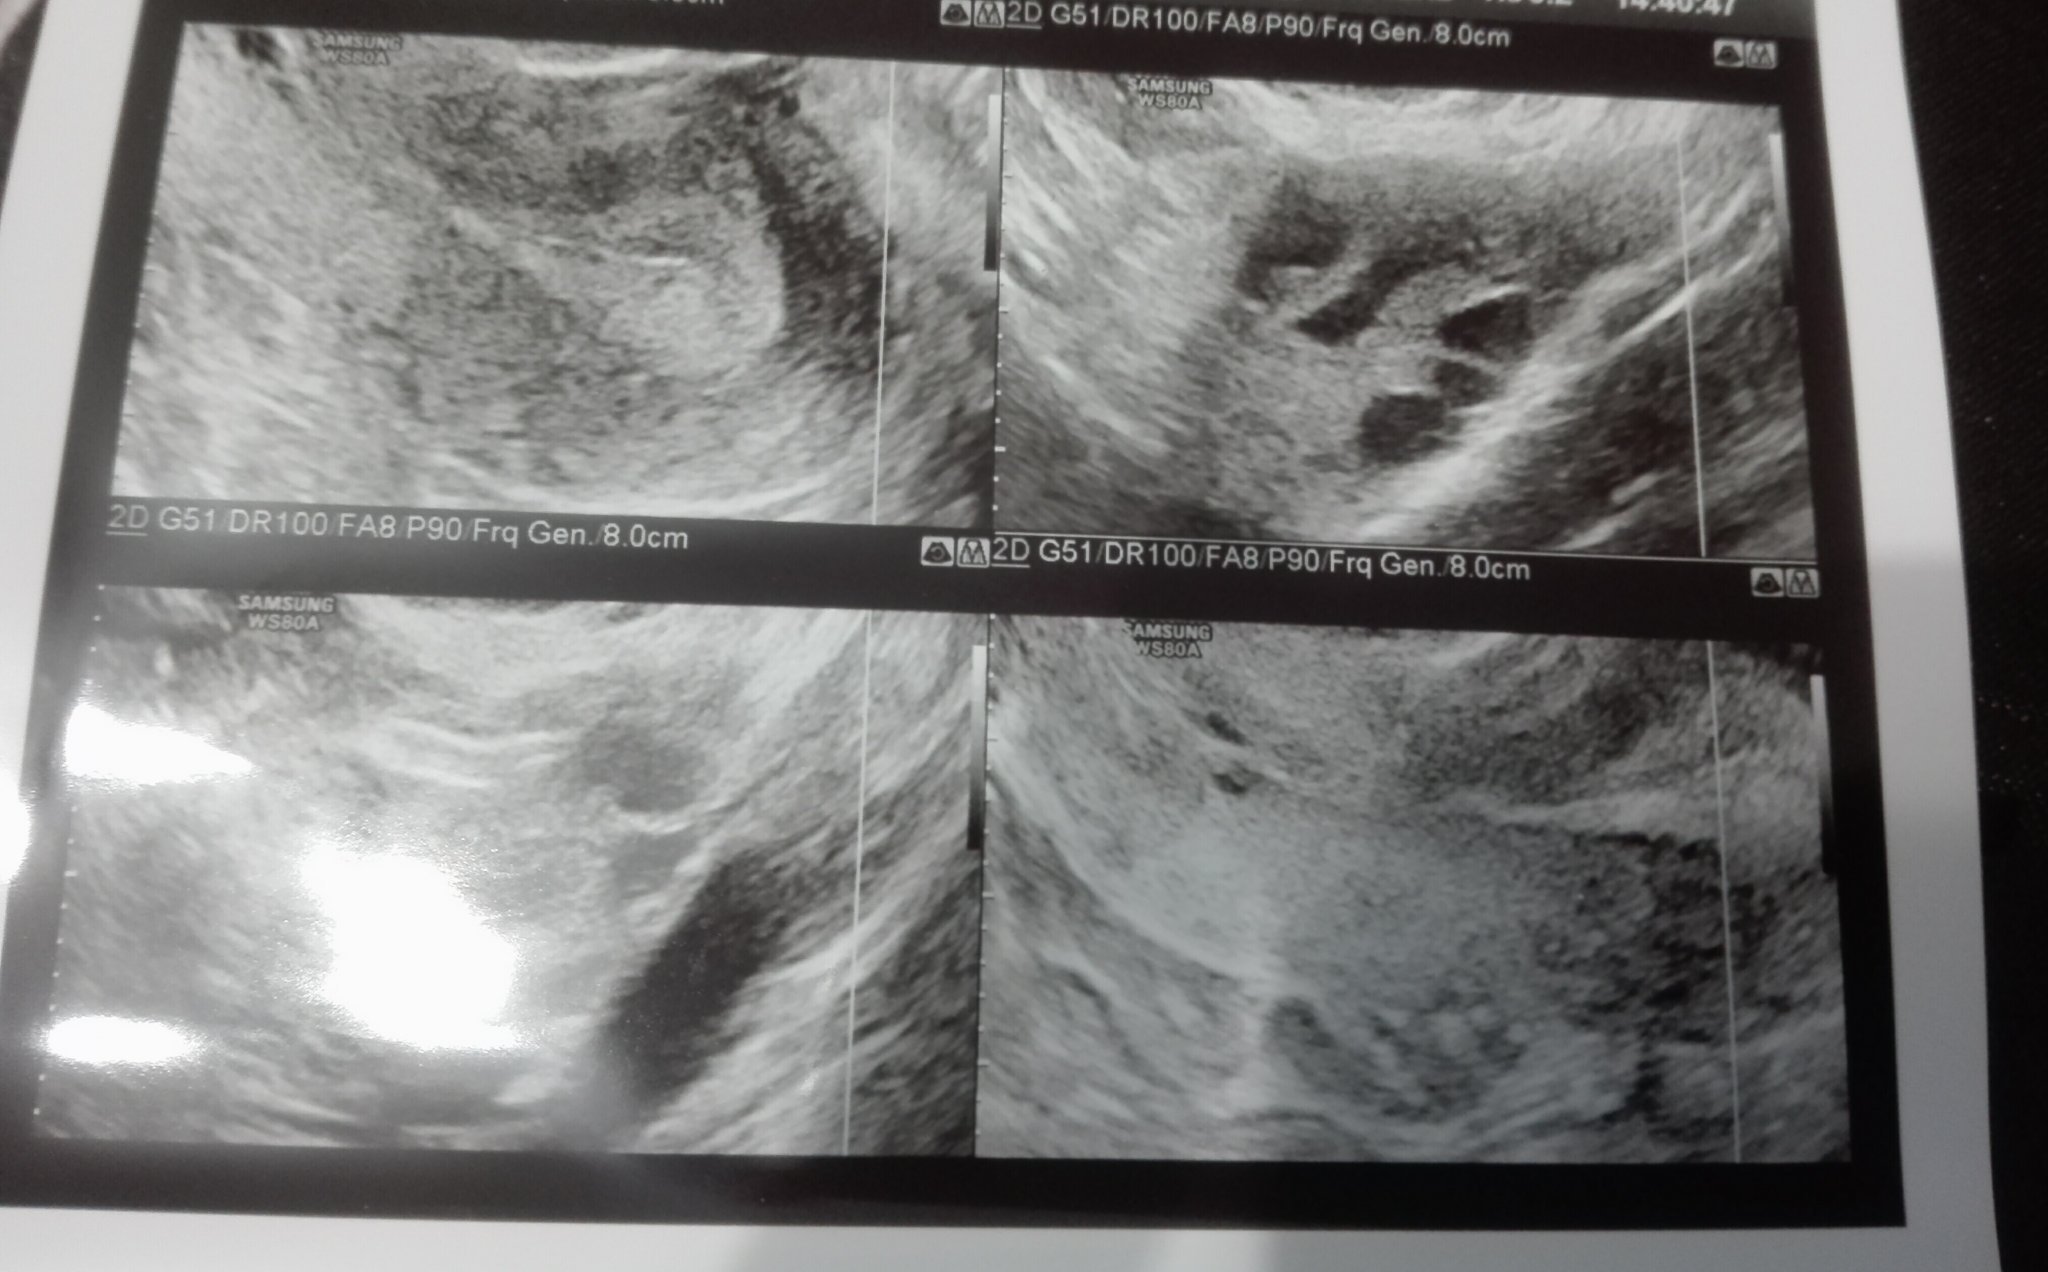

натрупва се яко, М закъснява, защото не е имало О да отключи процеса. Ама дано не ти идва от бебе де!! Споделям ти това, защото писа, че си се размислила за причини за удебелена лигавица. А те не са много... много се надявам да не ти дойде по хубава причина.